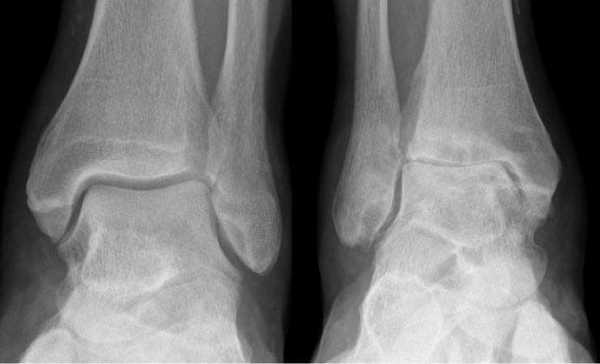

Артроз левого сустава. Суставная щель очень мала.

Остеоартроз голеностопа может быть трудно диагностировать до появления болезненных или изнурительных симптомов. Ранний остеоартроз часто диагностируется на рентген снимках, сделанных по другим причинам. В дополнении к рентгену голеностопа ортопед может использовать МРТ голеностопа и КТ голеностопа для диагностики остеоартроза. Как правило, ОА поражает оба сустава, поэтому ортопед назначает обследование сразу двух суставов. Другие диагностические исследования включают в себя анализ крови, чтобы исключить другие состояния, вызывающие боль в голеностопе, такие как ревматоидный артрит. Анализ синовиальной жидкости также позволяет определить, является ли подагра или инфекция основной причиной воспаления.